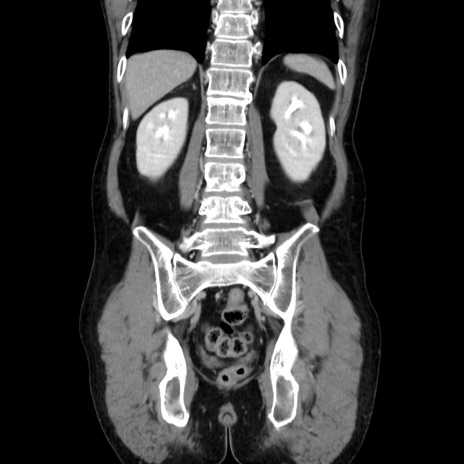

症例37(冠状断像)

【症例】40歳代 男性

【主訴】腹痛

【現病歴】4時間ほど前に電車に乗車中に臍部上より腹痛出現。徐々に増悪し起立困難となり、救急外来受診。生ものは数日食べていない。今朝お雑煮を食べた。

【身体所見】BT 36.8℃、BP 117/84mmHg、HR 91/min、SpO2 97%、苦悶様、腹部:臍上部広範囲圧痛あり、反跳痛±

【データ】WBC 8100、CRP 0.03